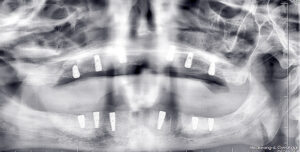

Cerrahi işlemin hemen ardından hastanın üst ve alt çenesine implantlar sorunsuz şekilde yerleştirildi. Ameliyat sonrası genel durumu stabil olan hastanın iyileşme sürecinin de problemsiz ilerlediği bildirildi.